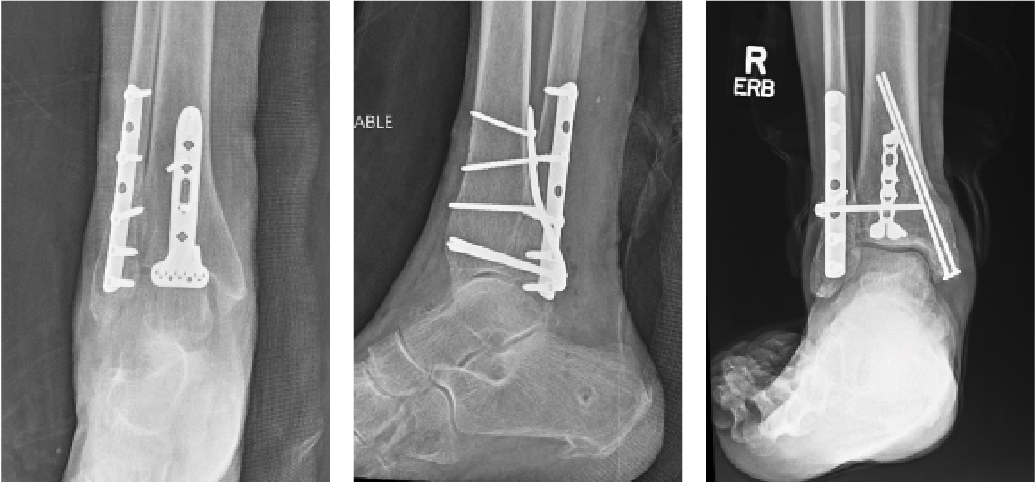

Open Reduction and Internal Fixation

Recent studies have advocated for open reduction and internal fixation (ORIF) as an acceptable method of treatment for geriatric ankle fractures in contrast to traditional conservative management.9,10 However, osteoporotic bone and comminuted fractures could present fixation challenges in the elderly population. Unfortunately, there is minimal evidence on specific plate technology on geriatric ankle fractures, and most literature debatably equates osteoporotic fractures to geriatric fractures.

The evolution of locking plate technology has shown its value when treating osteoporotic bone. Aigner and team performed a retrospective case-control study on over 300 patients with ankle fractures and an average age of 73 years. They found higher revision surgeries, complication rates, and implant failure with standard plating techniques versus locking plate technology.11 In contrast, Herrera-Perez and colleagues evaluated osteoporotic distal fibula fractures treated with locking plate fixation versus traditional plating in patients older than 64 years of age. They found a similar average time to union and AOFAS scores in each cohort. The only advantage noted was the earlier time to weight-bearing in the locking plate group, which can be especially advantageous to improve mobility and decrease rehabilitation time for the geriatric population.12 Disadvantages of standard ORIF and locking plate technology still remain as they can be costly, bulkier, and will likely require a larger soft tissue envelope insult, which may lead to increased complications.